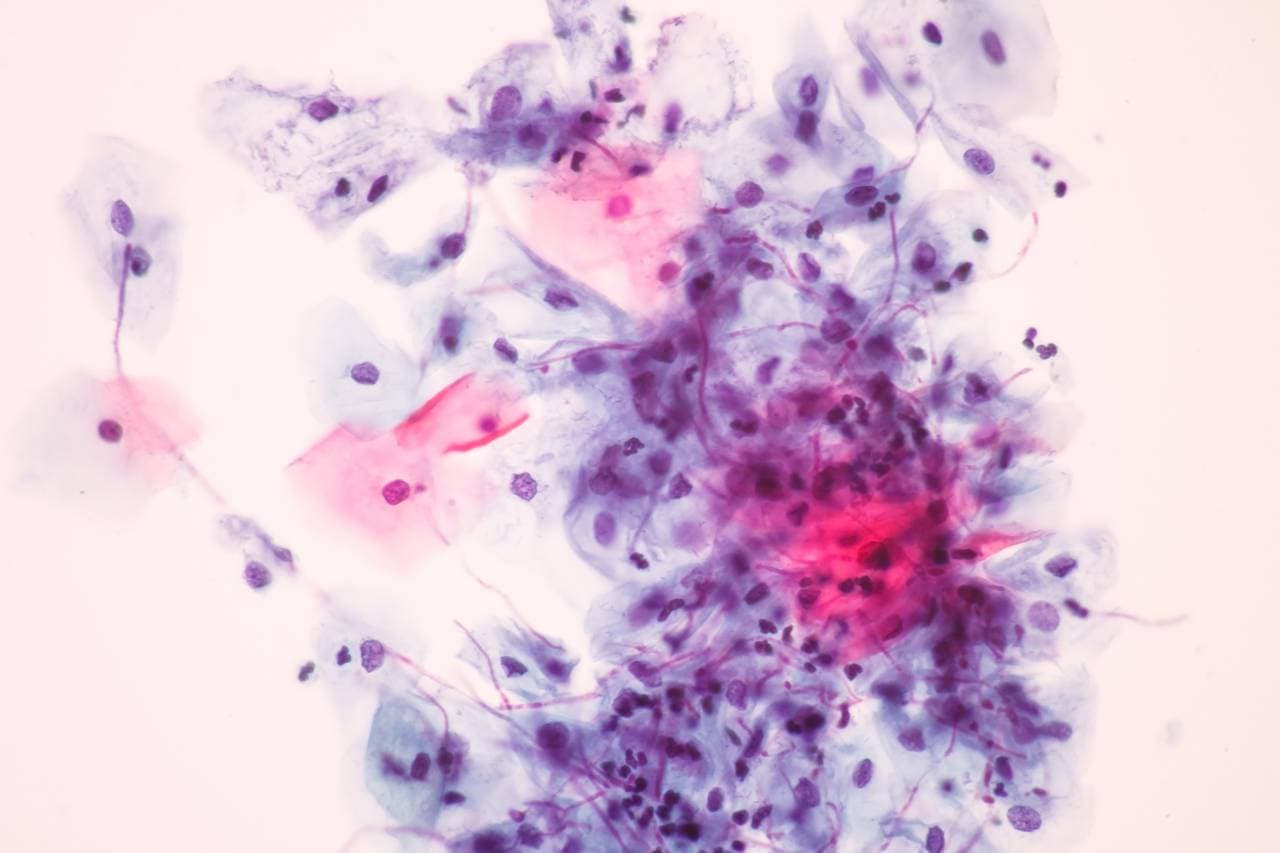

Candidoza este o infecție cauzată de una dintre cele peste 200 de specii de Candida, dintre care doar câteva sunt periculoase pentru organismul uman. Infecțiile fungice de acest tip pot fi superficiale sau invazive. Cele din prima categorie se manifestă, de obicei, la nivelul pielii sau al mucoaselor și pot fi tratate cu succes, prin medicamente antifungice. Infecțiile invazive pot duce la complicații severe, mai ales atunci când este vorba despre specii de Candida care sunt rezistente la medicamente.

Potrivit National Institute of Health din Statele Unite, specia care cauzează cele mai multe tipuri de Candida este Candida albicans. De obicei, ea se regăsește la nivelul tractului gastrointestinal sau genitourinar, dar și în flora conjunctivală sau bucală și nu reprezintă un pericol. Însă, pe fondul unui sistem imunitar deficitar sau al altor factori de risc, poate duce la infecții fungice ușoare sau severe.

Diagnosticarea candidozei

Este foarte importantă identificarea speciei de Candida care a produs infecția, pentru că în funcție de acest lucru se poate recomanda, mai departe, tratamentul adecvat. De exemplu, Candida albicans răspunde bine la azoli, în vreme ce alte specii, cum sunt Candida glabrata și Candida krusei sunt rezistente la acest antifungic. Identificarea tipului de ciupercă ce a generat infecția este esențială și pentru a putea preveni recurența acesteia.

De obicei, examinarea fizică este suficientă pentru a diagnostica infecția de la nivelul cavității bucale, al pielii sau al zonei genitale. Cu toate acestea, este posibil ca medicul să recomande analize și teste suplimentare, pentru un diagnostic precis.

Pe lângă metodele clasice de diagnostic, cum ar fi examenul microscopic și culturile din probe biologice, laboratoarele moderne folosesc tehnici molecular-bazate pentru a identifica rapid și precis speciile de Candida. Tehnologia PCR (Reacția de Polimerizare în Lanț) și secvențierea genetică permit detectarea chiar și a infecțiilor cu forme invazive, unde diagnosticul rapid este crucial pentru un tratament corect.

Aceste metode sporesc sensibilitatea și specificitatea diagnosticării, contribuind la evitarea tratamentelor empirice ineficiente și reducând riscul complicațiilor.